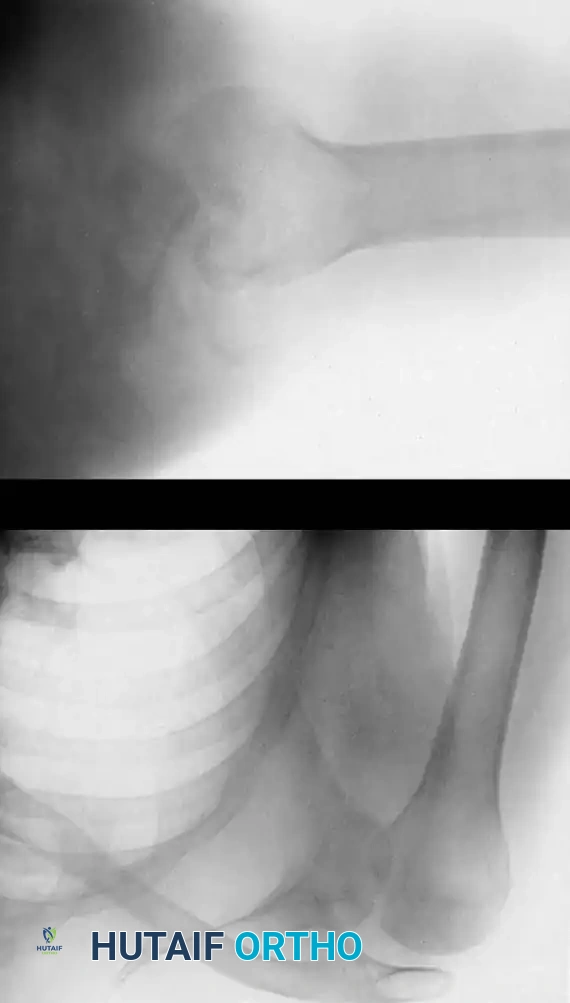

Imaging Strategy

A complete radiographic trauma series is mandatory, including true anteroposterior (Grashey) and axillary lateral views. The axillary view is the gold standard for confirming the direction of the dislocation and identifying engagement of the glenoid rim within the humeral head defect.

As emphasized by Kirtland et al., computed tomography (CT) with three-dimensional (3D) reconstruction is the definitive modality for evaluating bony injuries. CT accurately quantifies the percentage of articular surface damage on the humeral head, which is the primary determining factor in selecting the appropriate surgical intervention.

In chronic anterior dislocations, the posterolateral aspect of the humeral head is driven against the sharp anterior rim of the glenoid. This constant impingement produces a massive compression fracture. Because the patient repeatedly attempts to mobilize the joint, this defect is typically much larger and deeper than the classic Hill-Sachs lesion seen in recurrent, acute anterior instability.

Concurrently, the anterior glenoid rim suffers compression fractures, and in long-standing cases, a false joint or "pseudoarticulation" forms between the humeral head and the anterior scapular neck.

Chronic posterior dislocations produce a reverse Hill-Sachs lesion—a large compression fracture on the anteromedial aspect of the humeral head caused by impingement against the posterior glenoid rim. Similar to anterior variants, these defects enlarge over time due to the patient's continual, forceful attempts to increase their range of motion.